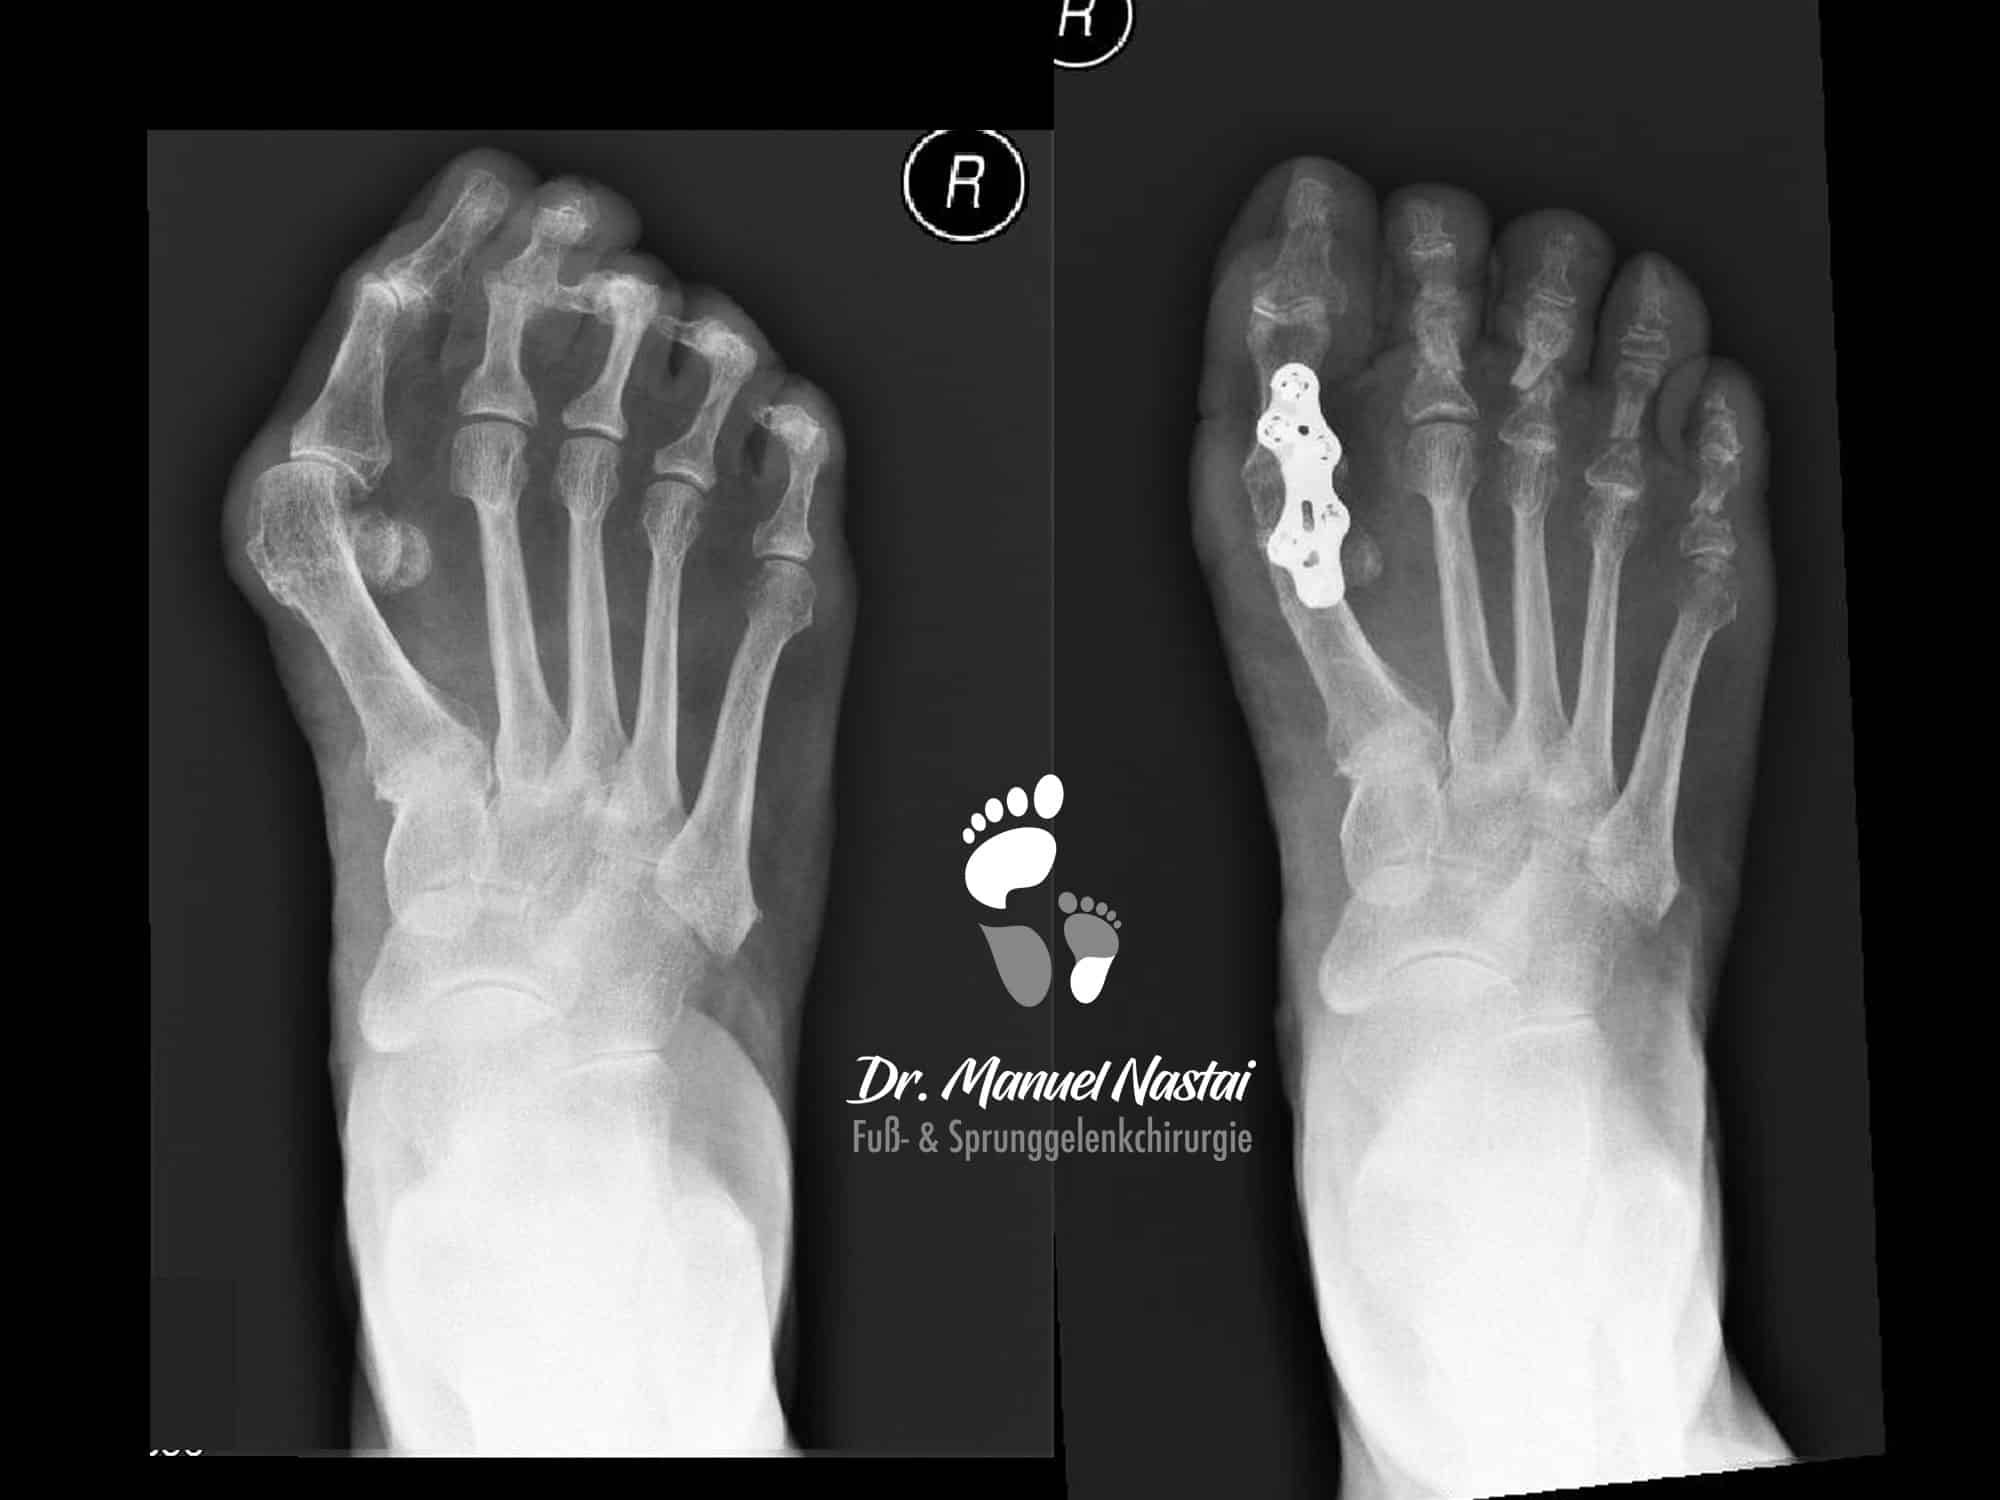

Hallux valgus